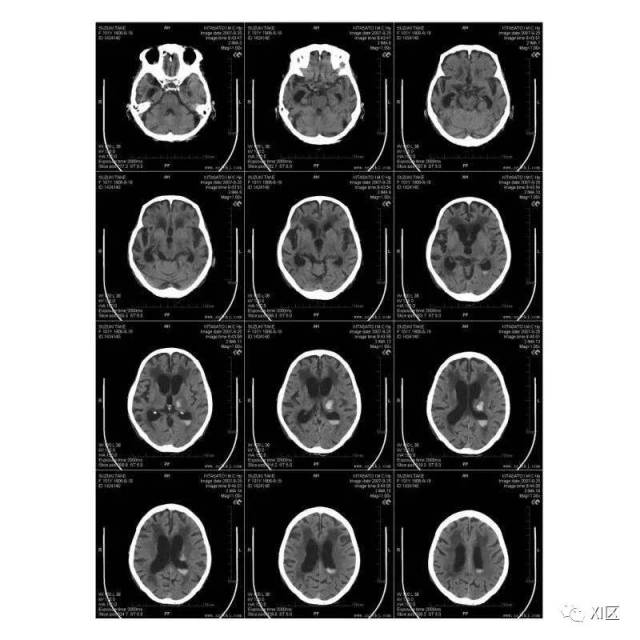

ct胶片,胶片底片

ct胶片上那些与剂量相关的参数!

ct胶片与核磁共振胶片扫描后有什么用途呢原来这么有用

应用office lens软件采集ct胶片影像

ct胶片

新型医用ct胶片,cr胶片,dr胶片